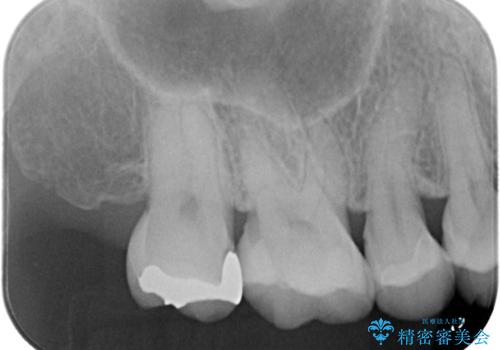

- 昔入れたメタルインレーの下にむし歯が再発したため治療を行った患者様です。

メタルインレーは汚れが付着しやすく、適合も悪いことがあるため、むし歯が再発しやすかったと思われます。